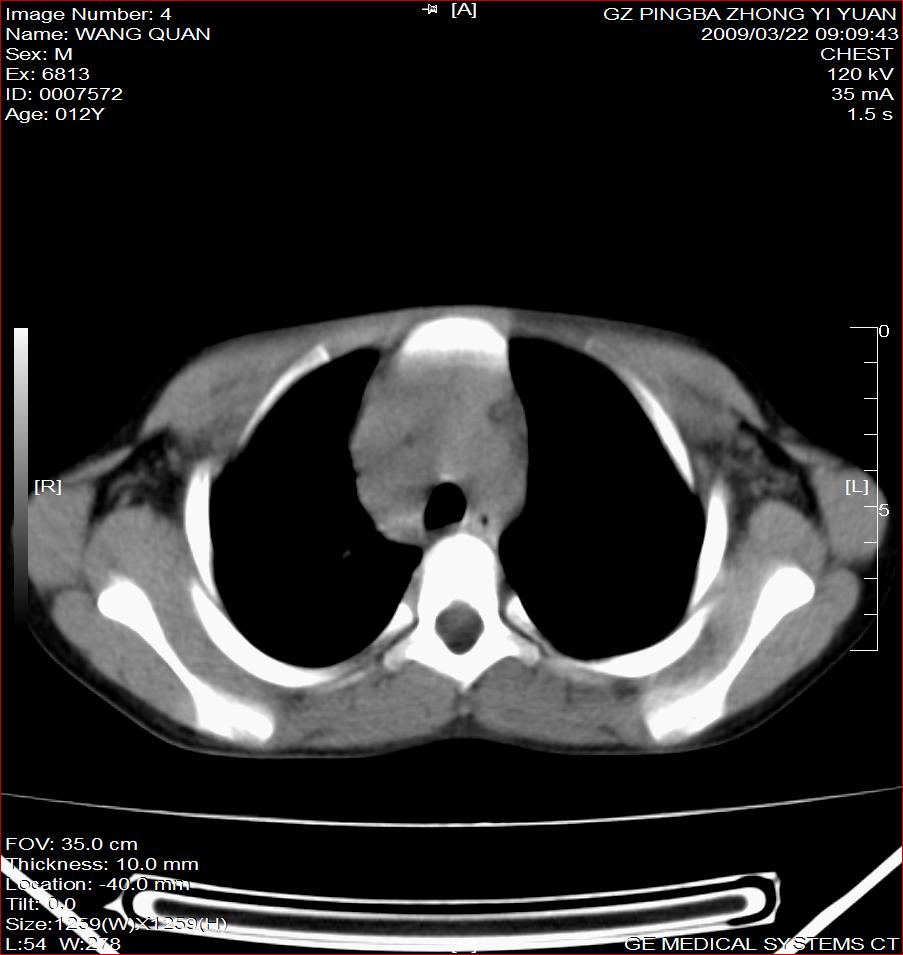

以下是引用随光逐影在2009-3-23 8:12:00的发言:[br]1)右肺门及纵隔淋巴结结核。2)两肺急性血行播散型肺结核可能。3)右侧支气管内膜结核?建议必要时行纤支镜检查。4)右侧少量胸腔积液。